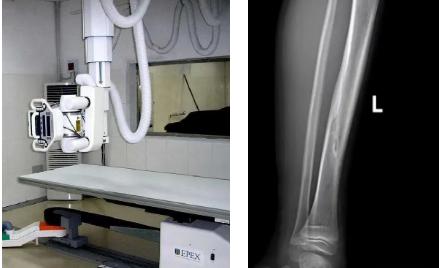

一般骨科創(chuàng)傷的病人,只要到影像科拍一張X光片,很快就會(huì)明確診斷有沒(méi)有骨折。然而有一些特殊類(lèi)型骨折的病人,由于拍片影像重疊的緣故,或者骨折未發(fā)生明顯移位,病變可能顯示不出來(lái),等過(guò)了一段時(shí)間后,骨折部位才能夠顯示清楚。這種類(lèi)型的骨折,叫做隱匿性骨折。若在臨床上診斷及時(shí)且明確,及時(shí)固定患者的骨折部位,進(jìn)行適當(dāng)治療并減少運(yùn)動(dòng),對(duì)患者的恢復(fù)有重要意義。

1.定期復(fù)查。一般于骨折后2-4周,骨折進(jìn)入骨痂期,骨折斷端有新生骨形成,呈明顯高密度,無(wú)論是X線或是CT,都能比較清晰觀察到,通過(guò)前后圖像對(duì)比,較容易診斷隱匿性骨折。

2.CT或MRI檢查。CT是斷面成像,不會(huì)出現(xiàn)重疊而導(dǎo)致漏診,同時(shí)CT還可以進(jìn)行多平面的重建,除了發(fā)現(xiàn)X線無(wú)法發(fā)現(xiàn)的骨折外,還可以三維直觀的顯示骨折的程度,對(duì)臨床治療有指導(dǎo)意義。CT無(wú)法發(fā)現(xiàn)骨裂、不全骨折或者骨挫傷,對(duì)軟組織的損傷診斷也有局限性,MRI就可以發(fā)現(xiàn)這些損傷。